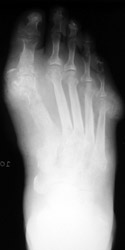

Gout: AP- Erosions 1st MTP joint with tophiGout: AP- Erosions 1st MTP joint with tophiTophaceus Gout: LateralTophaceus Gout: APGOUT is caused by monosodium urate or uric acid crystal deposition within cartilage, bone, or periarticular tissues.

First metatarsophalangeal joint is most commonly affected, followed by the first interphalangeal joint and tarsometatarsal joints. Posterior calcaneal involvement has also been noted. The majority of first presentations are monoarticular. Bilateral and symmetric or asymmetric polyarticular involvement may be present within any of the foot joints.

Acute, episodic soft tissue swelling may represent the earliest radiographic sign. Later, sharp, round or oval marginal joint erosions with sclerotic borders are classically seen with gout. These findings most commonly occur along the dorsum of the foot. Associated soft tissue tophi or intraosseous nodules may be present. "Overhanging margin" occur where the bone resorbs beneath a tophaceous nodule. Joint spaces are usually preserved, but ankylosis may rarely occur with advanced stages of gout. The aforementioned findings may be in different stages of progression with any given patient.

Concomitant osteoarthritis (especially of the tarsometatarsal joint) is common and should not be confused with gout. Joint space narrowing, as seen with advanced gout, may mimic rheumatoid arthritis.